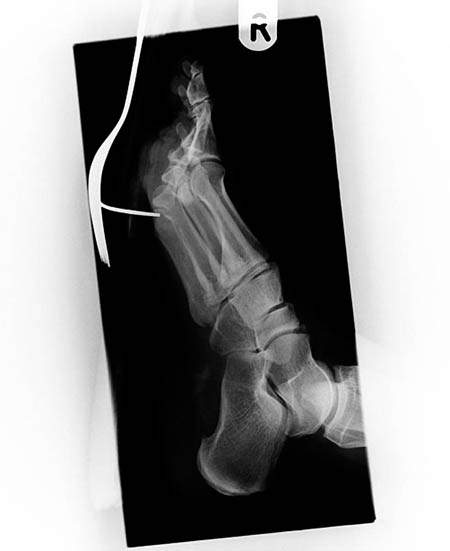

腳被釘子穿過